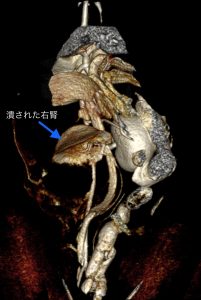

手術では、右の腎臓が10㎝以上の大きさに腫れており、中に赤黒いゼリー状の物質が詰まっていました。腫瘤は、後大静脈や左結腸動脈などの血管とべったり張り付いており、慎重に剥がして無事に摘出できました。

病理検査結果は、「腎周囲偽嚢胞と化膿性腎炎」でした。

一般的に腎周囲偽嚢胞は、いろんな原因で腎臓の周りに水のような物質が溜まる病気のはず…この猫ちゃんは、腎臓の周りに硬いゼリー状の物質が溜まってしまったため、腎臓が押し潰されて、ペチャンコになってしまっていました。